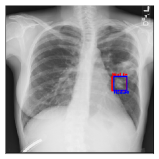

CXR8 [21] is one of the most commonly accessible radio-logical examination for many lung diseases. The data consists of 112,120 images collected by 30,805 patients. As shown in Table I, nine class labels of normal state and eight diseases including cancer are defined for classification. The data is divided into training set and test set, and the classification accuracy and ROC curve with several well-known deep network such as VGG16, GoogLeNet, and ResNet, are reported on the original paper [21]. In addition, 984 Bounding Boxes (B-Box) are provided for localization. Fig. 5 shows image examples of CXR8. The red rectangle in the image shows given B-Box.

Refer to caption

(a) Atelectasis

(b) Mass

Figure 5: Image examples of CXR8